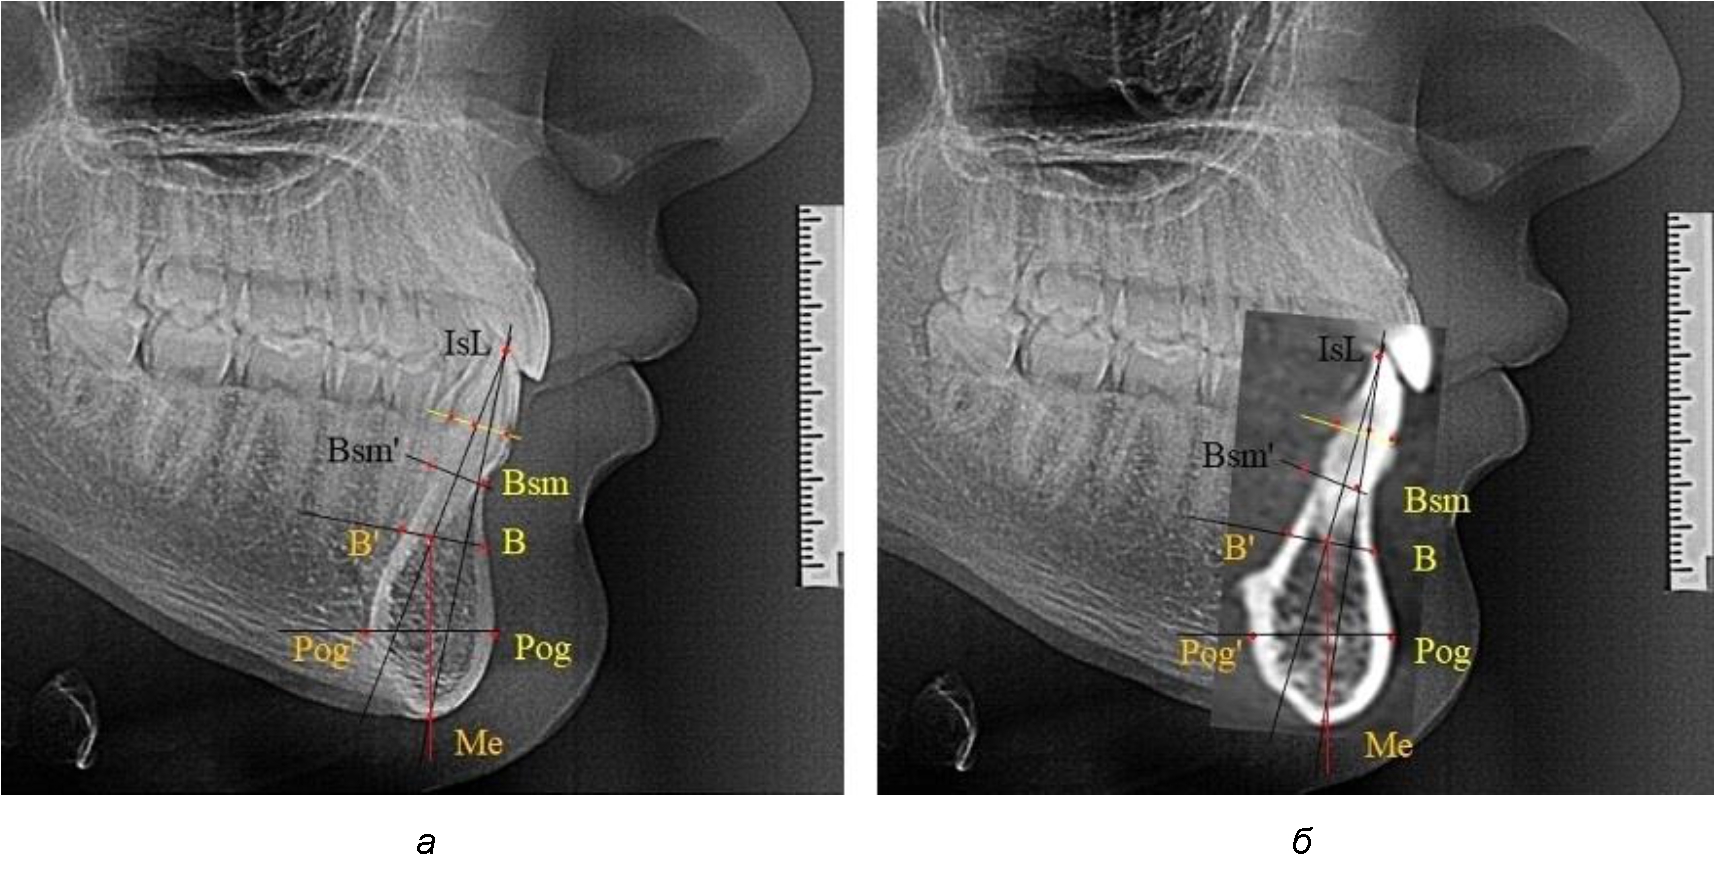

На режущем крае нижнечелюстного резцового сегмента устанавливалась точка, обозначаемая как IsL.

Определяли положение цервикальных точек резцов на вестибулярной и лингвальной поверхностях, которые соединяли цервикальной линией. Условная срединную вертикаль зуба соединяла резцовую точку IsL с серединой цервикальной линии и, как правило, доходила до апикальной точки, которую обозначали как Ap. Линия IsL–Ap определяла высоту зубоальвеолярной части резцового нижнечелюстного сегмента. Определяли высоту коронки и корня зуба. Кроме того, на вестибулярной поверхности зубочелюстного сегмента отмечали точку наибольшей вогнутости альвеолярной части, которая обозначалась как супраментальная точка Downs (Bsm). Измерялось расстояние IsL–Bsm, которое служило для определения проекции супраментальной точки Downs на язычную поверхность сегмента и обозначалась как точка Bsm'.

Проекцию верхушки корня резца на кость обозначалась как точка B нижнего апикального базиса по Schwarz. Соединяли апикальную точку с точкой нижнечелюстного апикального базиса линией, которая доходила до язычной поверхности подбородочного выступа и определяла положение точки B'. Таким образом, в зубоальвеолярной части сегмента выделялись две зоны: верхняя и нижняя, с последующим измерением по вертикали. При этом, как правило, верхняя зона была представлена компактной костной тканью, а в нижней зоне определялось наличие губчатой ткани между компактной пластинкой и стенкой альвеолы.

На нижнем контуре подбородочного выступа определяли положение ментальной точки Me. Линия, соединяющая апикальную точку с ментальной, определяла высоту подбородочного выступа тела нижней челюсти. Высота зубочелюстного сегмента IsL–Ме измерялась от резцовой до подбородочной точки. Вертикальная линия Ap–Me делила подбородочный выступ на две части: переднюю и заднюю (рис. 1).

Рис. 1. Ориентиры для исследования нативных препаратов (а) и рентгенограмм (б) резцового нижнечелюстного сегмента

При необходимости и/или возможности проведения КЛКТ-исследования проводили анализ с сопоставлением фрагмента, что повышало точность диагностических мероприятий (рис. 2).

Рис. 2. Фрагменты ТРГ с ориентирами для измерения параметров резцового сегмента (а) и с наложением фрагмента КЛКТ (б)